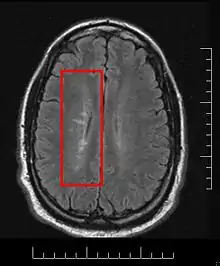

Dawson's Fingers appearing on an MRI scan

Multiple sclerosis is considered a disease of the white matter because normally lesions appear in this area, but it is also possible to find some of them in the grey matter.[30]

Due to the distribution of the lesions, since 1916 they are also known as Dawson's fingers.[40] They appear around the brain blood vessels.